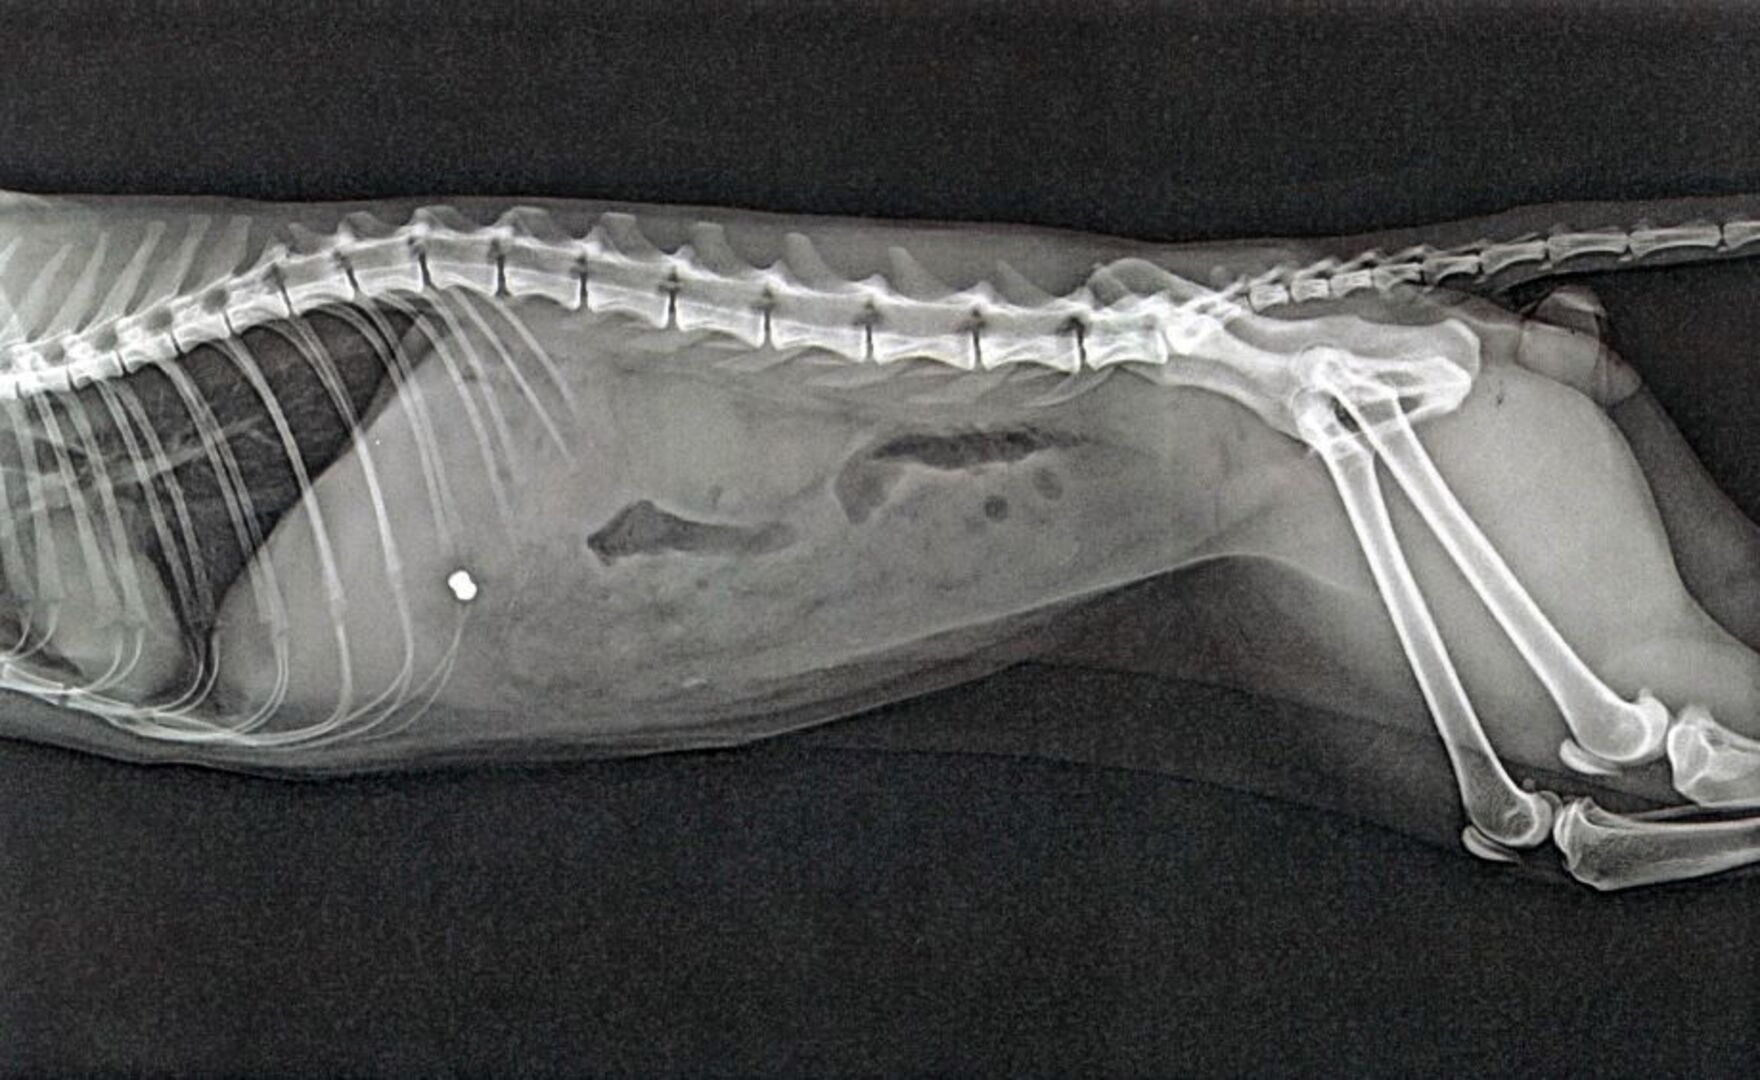

Sofort nach Entdeckung der Verletzung brachte die Katzenbesitzerin den Kater zum Tierarzt. Dort wurde das Tier geröntgt. Die Aufnahmen brachten dann die Diagnose: Der Kater wurde wohl mittels Luftdruckwaffe beschossen, denn deutlich war auf den Röntgenbildern ein so genanntes Diabolo-Projektil zu erkennen, welches an höchst lebensbedrohlicher Stelle in den Körper des Tieres eingedrungen war. Der Kater musste daraufhin eingeschläfert werden, da es keine Heilungschancen gab.

Das Bild zeigt die Verletzung des Katers. (externes Bild)